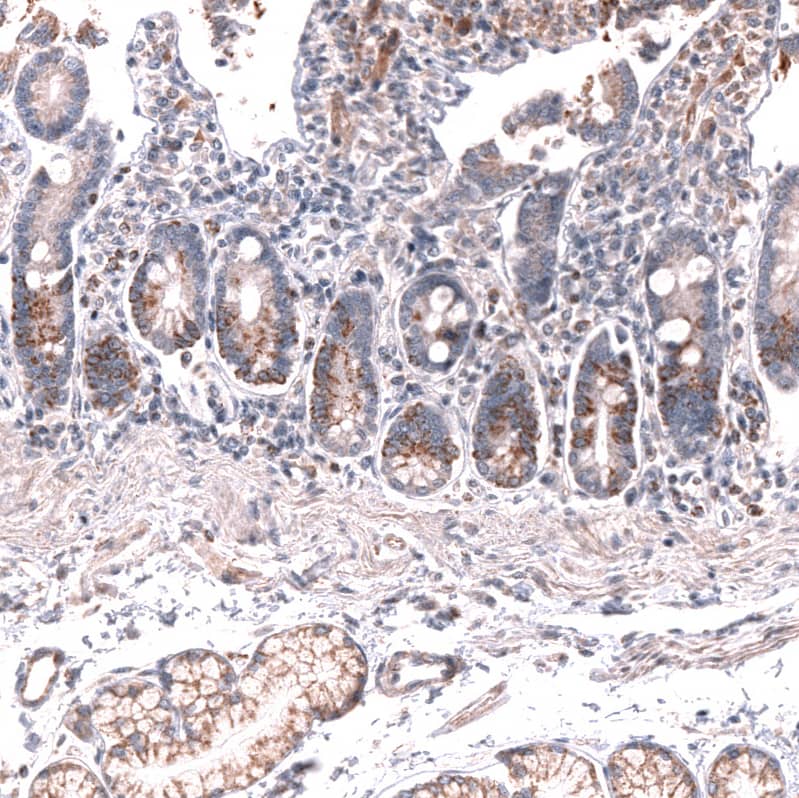

Immunohistochemistry-Paraffin: Lgr5/GPR49 Antibody (CL13579) [NBP3-24571]

Analysis in human placenta and tonsil tissues using NBP3-24571 antibody. Corresponding LGR5 RNA-seq data are presented for the same tissues.

Staining of human duodenum shows moderate cytoplasmic and membranous positivity in glandular cells.